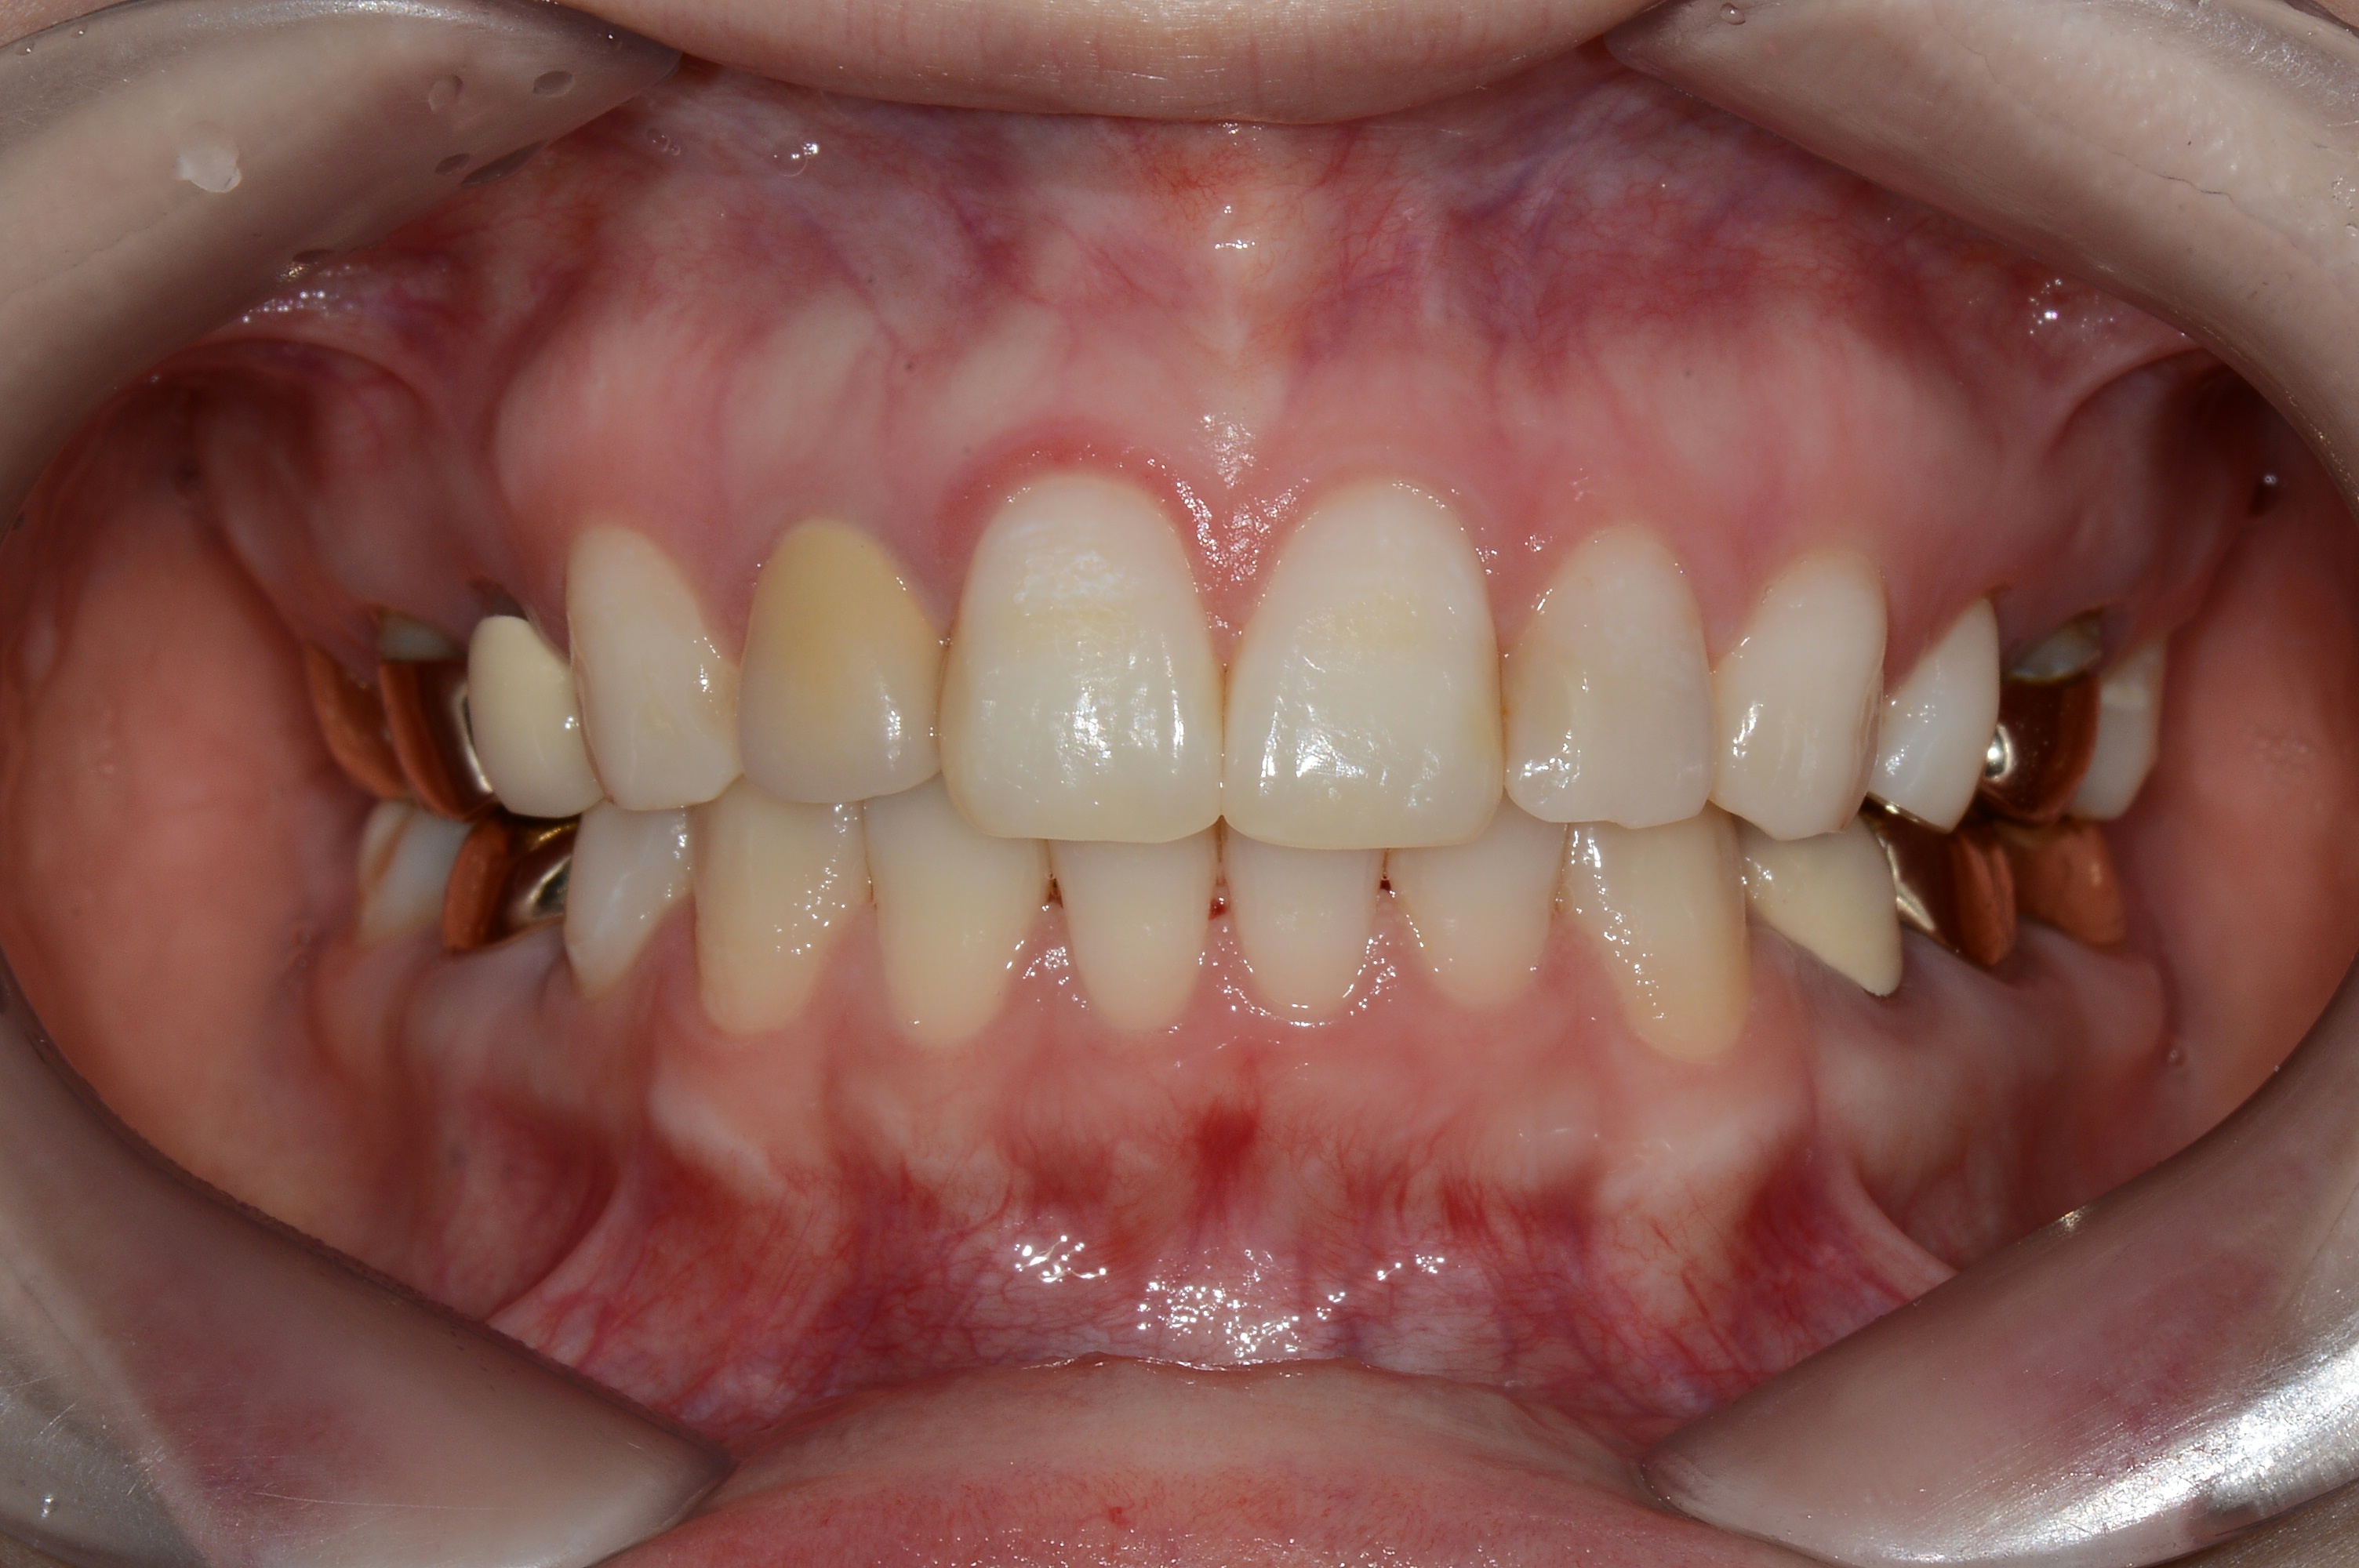

치료 전 사진입니다.